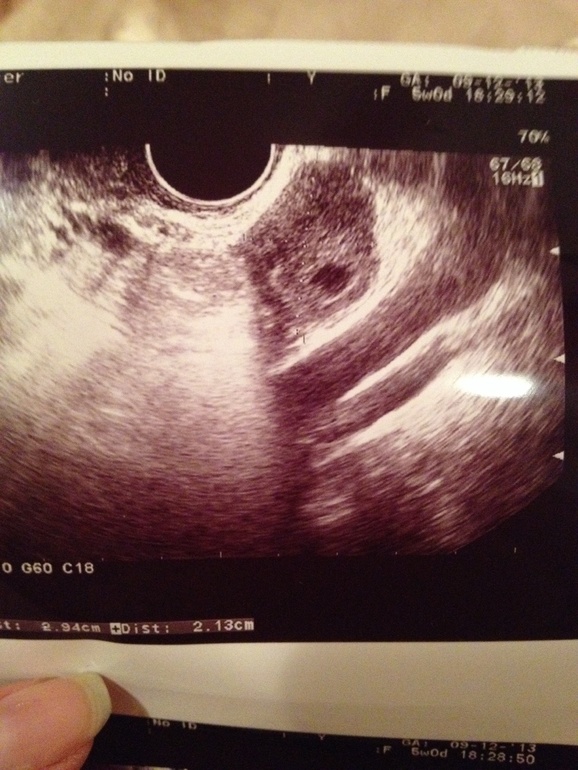

Неужели я увидела мою маленькую бусинку)она всего 5 мм)) а счастья дарит очень много)

Срок очень маленький, кроме точечки ничего не видно, но у меня акушерских 5 полных недель, а эмбриональных 2-3